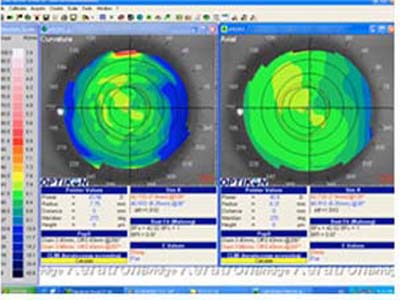

Con esta metodología, los poderes altos de la superficie corneal son representados en colores cálidos como el amarillo, naranja y rojo (Foto 2) mientras que las áreas de bajo poder se las representa en colores más frios como el verde y el azul. ( Foto 3), facilitandose así visualización de los efectos de la cirugía refractiva y la comprensión de sus resultados ( Foto 4 y 5)

Esta tecnología ha continuado evolucionando acorde a las necesidades de la practica médica y se diseñaron otro tipo de topógrafos que realizan un barrido con hendidura de luz sobre la córnea con movimiento horizontal o rotatorio y reconstruyen luego digitalmente las imágenes captadas pudiendo de esta manera hacer reconstrucciones tridimensionales que analizan las superficies por Elevación; se conocen como Topógrafos de Elevación. Esta nueva aproximación permite también hacer el análisis de las aberraciones corneales (Foto 7) per se desarrollando las ecuaciones de Zernicke con base a las irregularidades reveladas en los mapas de elevación.

6 - Topografía

7 - Aberraciones Corneales de Foto 6